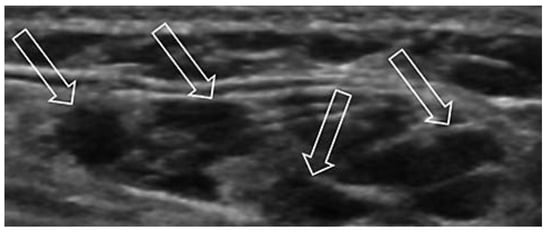

Case report A 22-year-old male experienced a presyncopal spell while studying for a university examination [...]